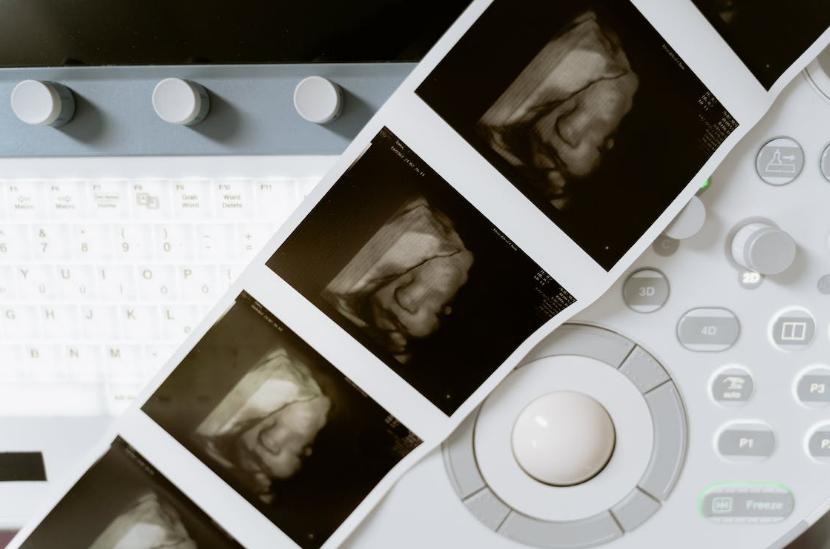

四维彩超最主要的功能是对胎儿进行各种检查,及早发现胎儿生长中出现的问题,如唇裂、脊柱裂等。另外,四维彩超的图像显示比传统彩超、B超更清晰、更准确。

三维彩超和四维彩超的区别在于维度不同,从而拍出的图片的效果也不同,三维彩超拍出的图片是直观立体图,而四维彩超增加了时间纬度,拍出的图片是动态立体图,也就是我们所说的动态视频,且更为清晰。

三维和四维彩超都可以用于孕期大排畸形检查,但是临床所使用的大排畸检查中使用四维彩超的较多,因为影像越清晰,胎儿畸形的检出率越高,想知道贵港四维彩超多少钱。

贵港牡丹妇产医院超声科引进原厂GE-8四维彩超检查机器。能够提高细节分辨率,满足从早孕期研究到复杂胎心的全程早期检查和诊断,清晰并动态记录宝宝在子宫内的活动和成长历程。